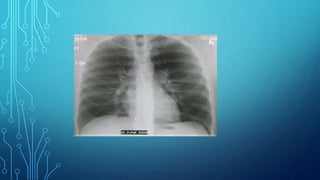

Fluorography - photographingan X-ray image from a fluorescent screen onto photographic film of various formats. Such an image is always reduced. In terms of information content, fluorography is inferior to radiography, but when using large- frame fluorograms, the difference between these techniques becomes less significant.

The main purposeof fluorography, associated with the speed of its implementation, is mass examinations to identify latent lung diseases (prophylactic fluorography). Fluorographic devices can be transported, therefore it makes it possible to carry out mass examinations in areas where there is no X-ray diagnostic equipment. Currently, film fluorography is being replaced by digital. Digital fluorography has all the advantages of digital radiography.